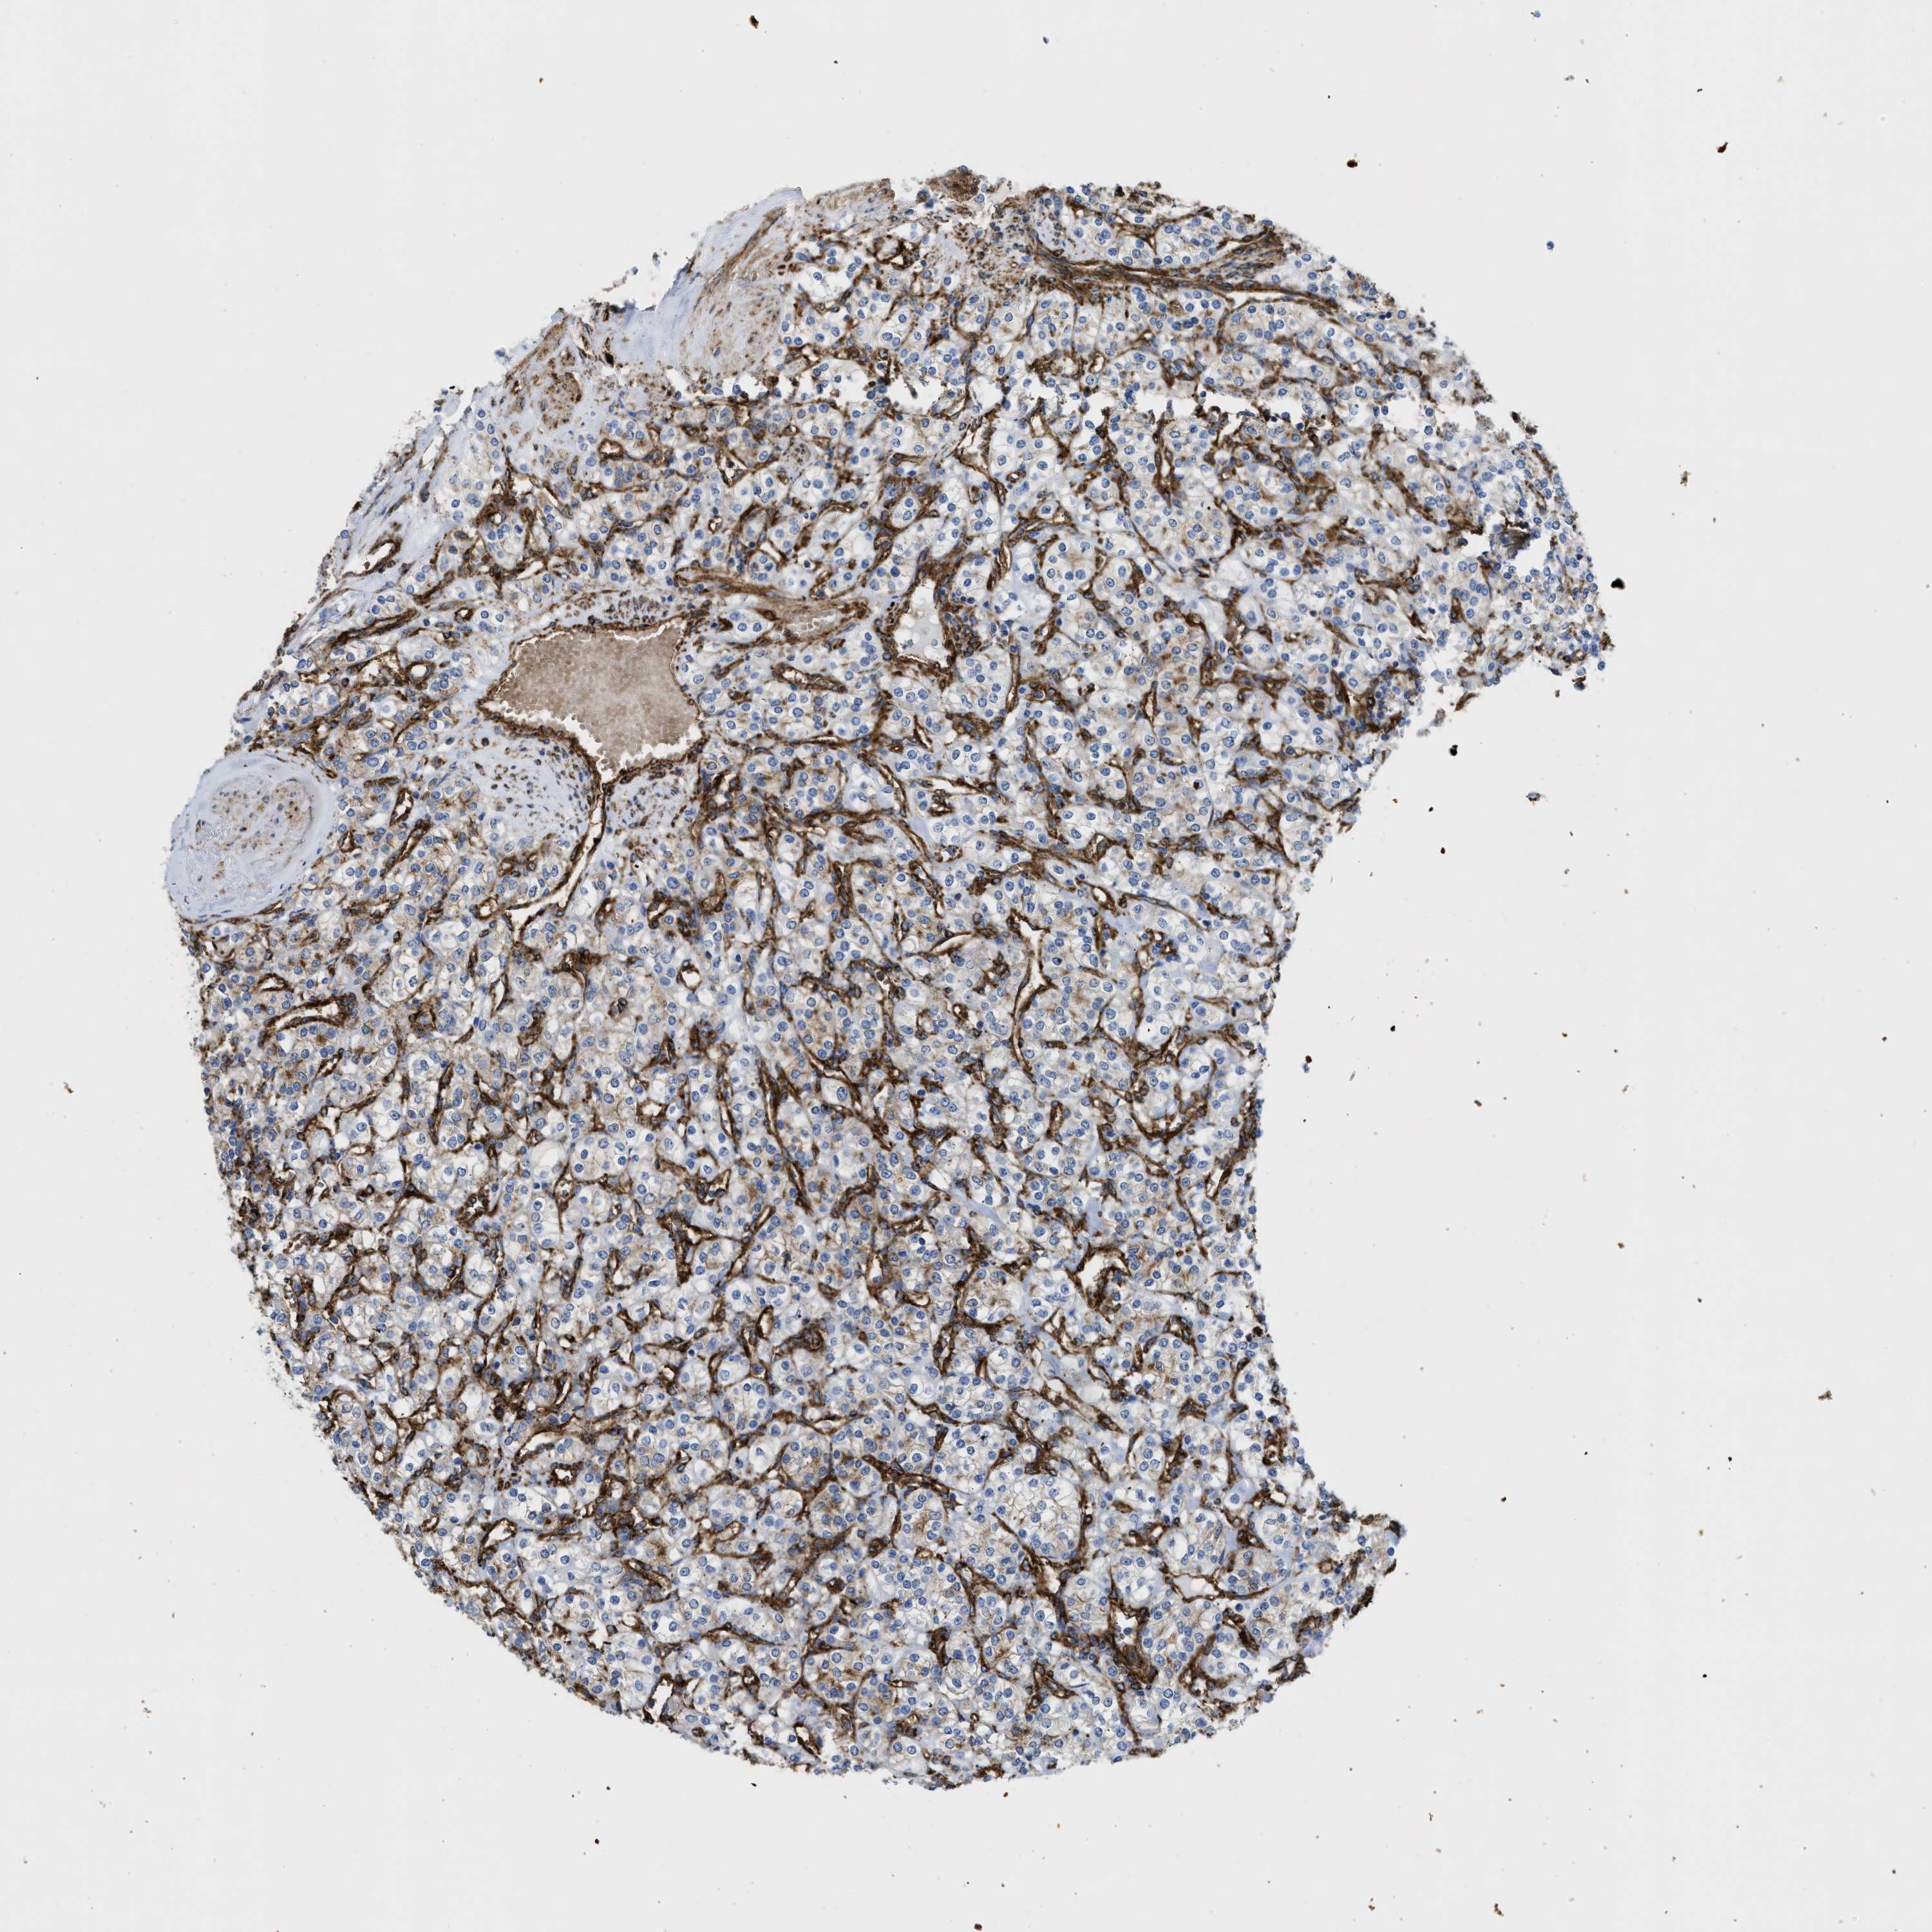

KIDNEY RENAL CLEAR CELL CARCINOMA (VALIDATION) - Interactive survival scatter ploti

The Survival Scatter plot shows the clinical status (i.e. dead or alive) for all individuals in the patient cohort, based on the same data that underlies the corresponding Kaplan-Meier plots. Patients that are alive at last time for follow-up are shown in blue and patients who have died during the study are shown in red.

The x-axis shows the expression levels (FPKM) of the investigated gene in the tumor tissue at the time of diagnosis. The y-axis shows the follow-up time after diagnosis (years). Both axes are complimented with kernel density curves demonstrating the data density over the axes. The top density plot shows the expression levels (FPKM) distribution among dead (red) and alive patients (blue). The right density plot shows the data density of the survived years of dead patients with high and low expression levels respectively, stratified using the cutoff indicated by the vertical dashed line through the Survival Scatter plot. This cutoff is automatically defined based on the FPKM cutoff that minimizes the p-score. The cutoff can be changed by dragging the vertical line or by entering a cutoff value in the square labeled "Current cut-off".

Under the Survival Scatter plot the p-score landscape (black curve; left axis) is shown together with dead median separation (red curve; right axis). Dead median separation is the difference in median mRNA expression between patients who have died with high and low expression, respectively. It is calculated as follows: median FPKM expression of dead patients with high expression - median FPKM expression of dead patients with low expression. This is intended to aid the user in visually exploring custom cutoffs and the associated p-scores and dead median separation.

Individual patient data is displayed and can be filtered by clicking on one or more of the category buttons on the top of the page. Categories describing expression level and patient information include: high, low, alive, dead, female, male and tumor stages. The scale of the x-axis can be toggled between linear and log-scale by clicking on the "x log" button. Mouse-over function shows TCGA ID, patient information and mRNA expression (FPKM) for each patient.

& Survival analysisi

Kaplan-Meier plots summarize results from analysis of correlation between mRNA expression level and patient survival. Patients were divided based on level of expression into one of the two groups "low" (under cut off) or "high" (over cut off). X-axis shows time for survival (years) and y-axis shows the probability of survival, where 1.0 corresponds to 100 percent.

HIP1 is validated prognostic, high expression is favorable in Kidney Renal Clear Cell Carcinoma (validation)

: 19.11

Average pTPM 17.6

Number of samples 100